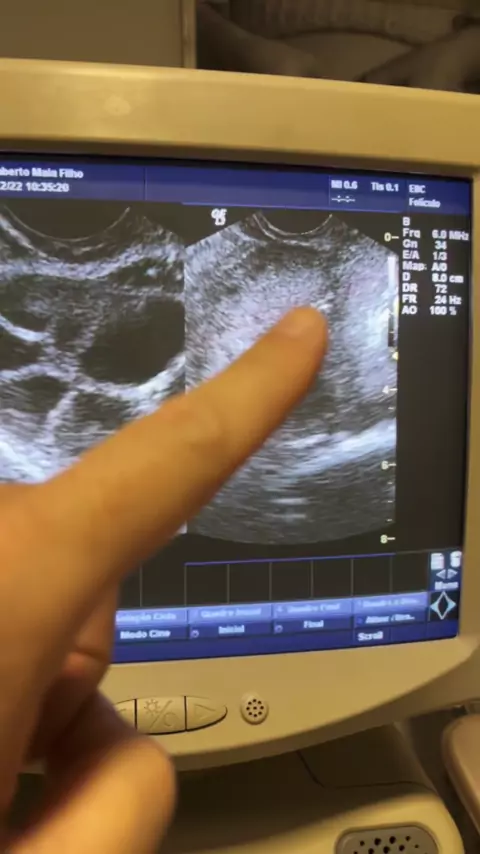

Vamberto Maia Filho

Congelamento de Óvulos com DIU? Sim! Totalmente… Não precisa retirar o DIU e durante o estímulo não muda nada. Então pra você que pensa em estimular a ovulação pra congelar seus óvulos não perca tempo!! Tempo são óvulos!!! 😊